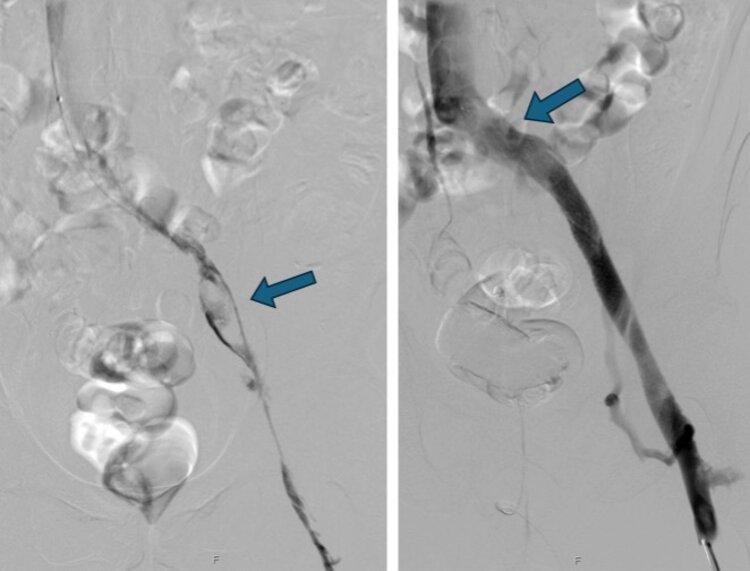

In der Regel erfolgt die Behandlung einer tiefen Beinvenenthrombose ambulant. In seltenen Einzelfällen bei ausgeprägten Thrombosen, unter Einbeziehung der unteren Hohlvene und der Beckenvenen, ist eine Behandlung im Spital ratsam. Hier können die Thrombosen medikamentös (sog. Lyse) oder mechanisch mittels eines minimalinvasiven Kathetereingriffs behandelt werden (s. Abbildung 3).